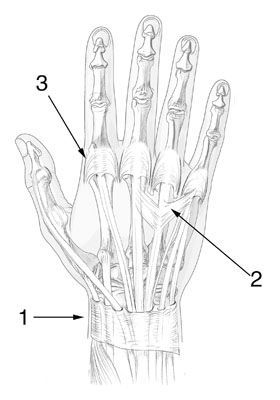

Mise au point Lésions récentes des tendons extenseurs de la main et des doigts , Christel Conso Institut Mutualiste Montsouris, Paris, France , Ph. Tchenio Hôpital Saint-Antoine - Paris , Christian Dumontier Hôpital Saint-Antoine, Paris, France N°155 - Juin 2006 ● 27 min de lecture

Mise au point Comment améliorer la chirurgie des tendons de la main , M. Merle Michel MERLE : Chef du Service de Chirurgie Plastique et Reconstructrice de l'Appareil Locomoteur au CHU de NANCY - Hôpital Jeanne d'Arc - 54201 TOUL , Gilles Dautel Hôpital d'Enfants, CHU Brabois, Vandoeuvre, France , Christian Dumontier Hôpital Saint-Antoine, Paris, France N°75 - Juin 1998 ● 21 min de lecture